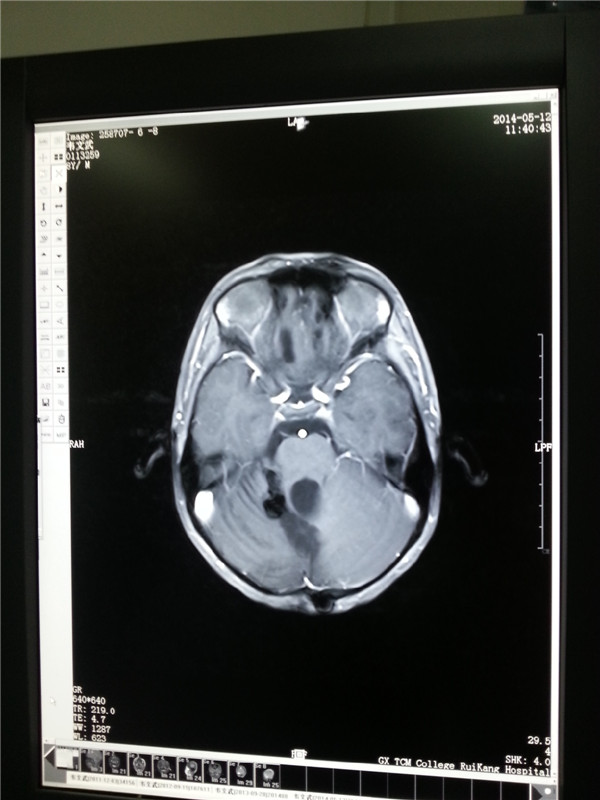

2013.9肿瘤消失(左图);2014.5复查肿瘤无复发(右图)